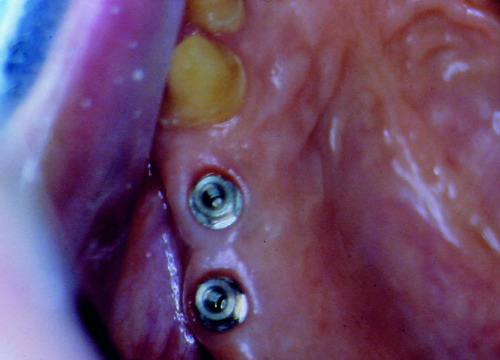

LA OCLUSIÓN MUTUAMENTE PROTEGIDA ES UN VIEJO CONCEPTO QUE CONSISTE EN LA MUTUA INTERACCIÓN DE LOS DISTINTOS GRUPOS DENTARIOS ENTRE SI. DE ESTA FORMA, LA TABLA PREMOLAR / MOLAR DE AMBOS HEMIMAXILARES ANTAGONISTAS, DETIENEN EL CIERRE MANDIBULAR EN CÉNTRICA, LOS CANINOS DISCLUYEN LAS PIEZAS POSTERIORES DURANTE LAS TRANSTRUSIONES, Y EL GRUPO INCISIVO LO MISMO DURANTE LAS PROPULSIVAS. SIN EMBARGO, DICHO CONCEPTO ES LIMITADO A LAS PIEZAS DENTARIAS, SIN TENER EN CONSIDERACIÓN LA IMPORTANTE FUNCIÓN QUE RECAE SOBRE LA ATM Y EN EL SOPORTE DE PRESIONES DURANTE ESTA DINÁMICA. ES ASI QUE EN EL AÑO 1981, EL DR. ANIBAL ALONSO GENERA EN LA CIUDAD DE BUENOS AIRES UN CONCEPTO MAS AMPLIO QUE DENOMINÓ : OCLUSION MUTUAMENTE COMPARTIDA. REF I EN EL QUE AMPLÍA EL CONCEPTO ANTERIOR, HACIENDO PARTÍCIPE A LA ATM EN LA MISMA. CUANDO EXISTE CARENCIA DE PIEZAS DENTARIAS POSTERIORES, YA SEA DE UN SOLO LADO O DE AMBOS , EL CIERRE MANDIBULAR ES DETENIDO POR LAS PIEZAS RESTANTE, FORZANDO A LA ATM A SOPORTAR PRESIONES MUY SUPERIORES A AQUELLAS PARA LAS QUE ESTA PREPARADA. FIG1 FIG2 FIG3 LUEGO DEL ESTUDIO CLÍNICO DE RIGOR, DONDE SE EVALÚA RADIOGRÁFICA Y PERIODONTALMENTE, SE PROCEDE A TOMAR MODELOS DE ESTUDIO Y MONTAR EN ARTICULADOR SEMIAJUSTABLE, SOBRE EL CUAL SE REALIZA UN ENCERADO PROGRESIVO DE DIAGNÓSTICO, A PARTIR DEL CUAL SE CONFECCIONA UN JUEGO COMPLETO DE PROVISIONALES DE AMBAS ARCADAS , INCLUYENDO LAS PIEZAS FALTANTES. SE ABORDA EL CASO YA QUIRÚRGICAMENTE DONDE EN UNA PRIMERA ETAPA SE TALLAN PRIMARIAMENTE LAS PIEZAS DENTARIAS Y SE PROCEDE, EXODONCIANDO EL INCISIVO CENTRAL SUPERIOR DERECHO, A REALIZAR UNA ROG(REGENERACIÓN ÓSEA GUIADA), PARA INMEDIATAMENTE INSTALAR PARTE DE NUESTROS PROVISORIOS EN LA GUIA ANTERIOR. SE ADAPTAN A LOS SECTORES POSTERIORES LAS PRÓTESIS REMOVIBLES QUE PORTABA, Y SE ESPERAN CUATRO MESES, AL CABO DE LOS CUALES SE REALIZA UN ESTUDIO CON DENTASCAN, MEDIANTE EL USO DE UNA FÉRULA RADIOLÓGICA CON TUBOS METÁLICOS , QUE NOS SERVIRÁ TAMBIÉN DE GUÍA QUIRÚRGICA. PROCEDEMOS ENTONCES A LA IMPLANTACIÓN DE LOS SECTORES EDÉNTULOS MEDIANTE IMPLANTES ROSCADOS Y TÉCNICA SEMI SUMERGIDA. TRANSCURRIDAS OCHO SEMANAS OBSERVAMOS UNA CORRECTA SALUD PERIMPLANTARIA, Y REALIZAMOS LA INSTALACIÓN DE LOS ABUTTMENTS ALCANZAMOS ENTONCES EL PUNTO EXACTO DONDE DEBEREMOS COMENZAR A RECONTRUIR EN FORMA PERMANENTE. PAZ DEL SISTEMA: CENTRICIDADARTICULAR-PAZ MUSCULAR-ESTABILIDAD- -ACOPLAMIENTO. BASES FUNDAMENTALES DE LA OCLUSIÓN ORGÁNICA FIG41 FIG42 PROCEDEMOS NUEVAMENTE A TOMAR IMPRESIONES, EN ESTE CASO DEFINITIVAS , MONTAR NUEVAMENTE EN ARTICULADOR, Y CONSTRUIR LAS RESTAURACIONES PERIFÉRICAS TOTALES EN BASE A PORCELANA SOBRE ORO GALVANIZADO. REF. II SOBRE LAS MISMAS TERMINADAS Y YA EN BOCA, CHEQUEÁMOS TODOS LOS ELEMENTOS QUE CONSTITUYEN UNA REHABILITACIÓN ORAL INTEGRAL, DESDE LA SALUD ENDODONTICA DE PIEZAS TRATADAS O NO, LA SALUD PERIODONTAL, EL AJUSTE PERIFÉRICO DE LAS RESTAURACIONES, LA ESTABILIDAD EN LA ATM, Y LAS FUNCIONES OCLUSALES, CHEQUEOS ESTOS QUE SE REPETIRAN EN CADA UNO DE LOS CONTROLES POST OPERATORIOS. FIG46 FIG47 FIG48 FIG66 FIG67 REFERENCIAS: REF I: OCLUSIÓN Y DIAGNÓSTICO EN REHABILITACIÓN ORAL REF. II ELECTROFORMACIÓN EN ODONTOLOGÍA RESTAURADORA.